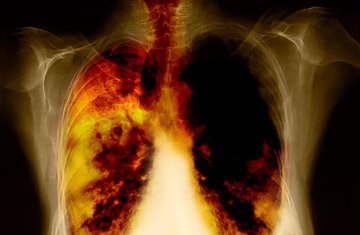

Cancro ai polmoni: smettere di fumare fa vivere più a lungo

Smettere di fumare fa sempre bene, e questo vale anche nel caso del cancro ai polmoni.

I malati che dicono basta alle sigaretto dopo una diagnosi di tumore ai polmoni raddoppiano infatti sopravvivenza alla malattia.